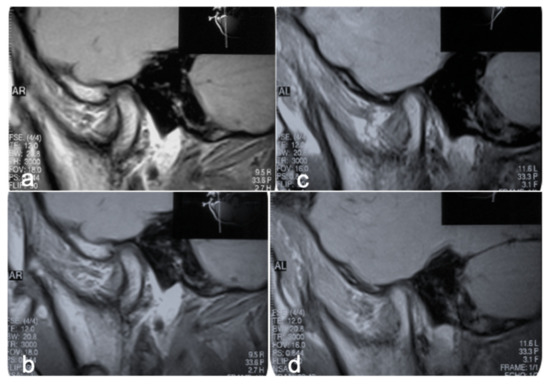

- Minervini, G.; Nucci, L.; Lanza, A.; Femiano, F.; Contaldo, M.; Grassia, V. Temporomandibular disc displacement with reduction treated with anterior repositioning splint: A 2-year clinical and magnetic resonance imaging (MRI) follow-up. J. Biol. Regul. Homeost. Agents 2020, 34, 151–160. [Google Scholar]